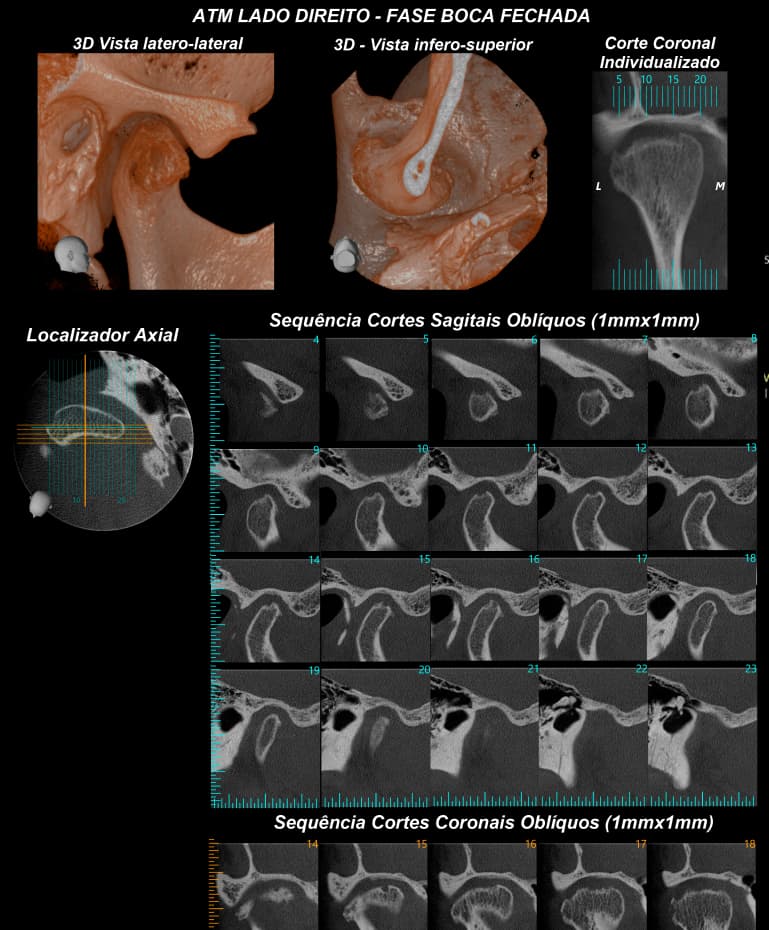

- Radiografia da ATM boca aberta e boca fechada

TOMOGRAFIA COMPUTADORIZADA DE ALTA RESOLUÇÃO por feixe Cone Bean - MORITA X800

- ATM´s